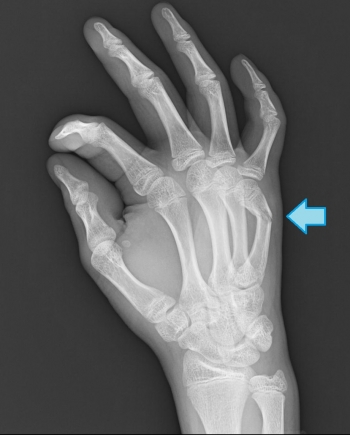

中節骨骨折

基節骨と比べると頻度は低い。

頚部骨折、骨幹部骨折、基底部骨折に分けられる。

頚部骨折

小児に発生するまれな骨折

中節骨の頚部に剪断力が働いて発生し、腱の停止部を持たない骨頭が背側に回転することもある。

骨幹部骨折

骨折部が浅指屈筋腱付着部より近位部の骨折の場合、背側凸変形

骨折部が浅指屈筋腱付着部より遠位部の骨折の場合、掌側凸変形